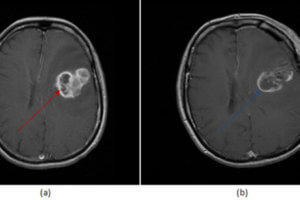

Radiation Necrosis

Radiotherapy is commonly used as an adjuvant therapy to surgery and chemotherapy in the management of primary brain neoplasms. Radiation destroys cells and damages the tumor blood supply. Addition of radiation therapy... Read more »

Residual/Recurrent Tumor

Imaging plays an important role in the diagnosis and management of patients with primary brain neoplasms. In particular, imaging is typically performed within 48 hours of tumor resection. Read more »